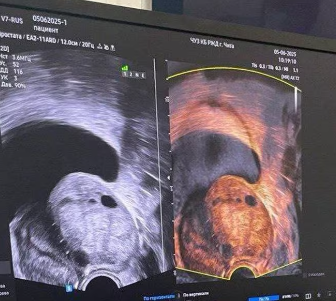

В клинике «ВеронаМед» теперь проводят фьюжен-биопсию простаты — современный метод, объединяющий МРТ и УЗИ для точного выявления подозрительных участков.

В клинике «ВеронаМед» теперь доступна инновационная процедура — фьюжен-биопсия простаты. Этот современный метод сочетает в себе аналитику методов магнитно-резонансную томографию (МРТ) и ультразвуковое исследование для точного определения подозрительных участков. Благодаря этому подходу врачам удается максимально точно локализовать и взять образцы ткани для диагностики, что повышает вероятность своевременного выявления рака простаты и снижает число повторных процедур. Для пациента это означает более точную диагностику, раннее обнаружение заболеваний и возможность начать лечение на ранних стадиях.

Преимущество фьюжен-биопсии заключается в высокой точности диагностики: благодаря совмещению изображений, врачи могут точно локализовать даже малейшие аномалии, которые могут быть пропущены при стандартной слепой биопсии, основанной только на УЗИ. Это особенно важно при выявлении ранних стадий рака простаты, когда опухоль еще невелика и трудно обнаружима.

В отличие от обычной биопсии, где образцы ткани берутся случайно или в предполагаемых зонах, фьюжен-метод позволяет целенаправленно взять образцы именно из подозрительных участков, что повышает вероятность постановки точного диагноза. Это уменьшает необходимость повторных процедур, сокращает время диагностики и повышает шанс раннего обнаружения заболевания.